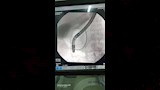

نجح فريق طبي بمستشفى أشمون العام بمحافظة المنوفية، اليوم الخميس، في إجراء أول عملية منظار للقناة المرارية (ERCP) داخل مستشفيات المحافظة، بعد أن كانت تُجرى سابقًا فقط في معهد الكبد القومي.

قاد الفريق الطبي الدكتور إبراهيم ناصر مدير المستشفى، وشارك فيه كل من: الدكتور عبدالعليم هلال، والدكتور أحمد هلال، والدكتور محمد ممدوح، والدكتور علاء عبد ربه، والدكتور أحمد تعيلب، بمساندة فريق تمريض العمليات وقسم الجراحة، حيث تمكنوا من إزالة الدعامة القديمة واستخراج الحصوات من القناة المرارية وتركيب دعامة جديدة بنجاح.

وساعد وصول جهاز المنظار الجديد المتبرع به الأسبوع الماضي في تمكين الفريق الطبي من إجراء العملية بدقة عالية داخل المحافظة دون الحاجة لتحويل الحالات لمراكز خارجية.